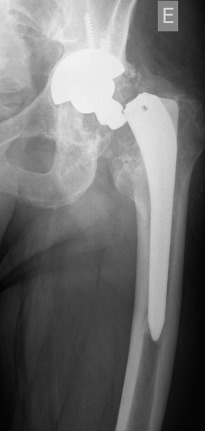

In October 2013 (two years and one month after the revision procedure), the patient was surprised by a storm and was struck by lightning while strolling. He remained conscious and suddenly he was unable to bear weight on the left leg and a deformity on his left lower extremity was detected. His neurovascular status was stable. Plain radiographs demonstrated a displaced fracture through the base of the neck of the femoral component (Fig. 3 ). The patient underwent revision THA through a posterior iterative approach. A transfemoral osteotomy was required to extract the stem, which presented no signs of loosening. Prophylactic Dall-Miles wiring was done to prevent fractures just under the osteotomy. The selected component for the revision was a modular curve Revitan® (Zimmer, Winterthur, Switzerland) system. It was a 200 × 180 mm stem with a distal locking screw of 36 mm and a metaphysis of 75 mm with 15° of anteversion. The head was a #36 metallic. Finally, the osteotomy was fixed with four Dall-Miles cerclages (Fig. 4 ). After the surgery, the patient needed two blood transfusions due to postoperative anaemia. The postoperative course was otherwise unremarkable and the patient was allowed partial two-crutch assisted weight-bearing. The patient was discharged with an active range of motion of 75° of hip flexion and 15° of hip abduction. Three months after surgery, the radiographs demonstrated consolidation of the osteotomy. After one year, the patient is satisfied, without pain and had returned to work.

Fig. 4. Postoperative radiograph after second revision with four Dall-Milles cerclages. |